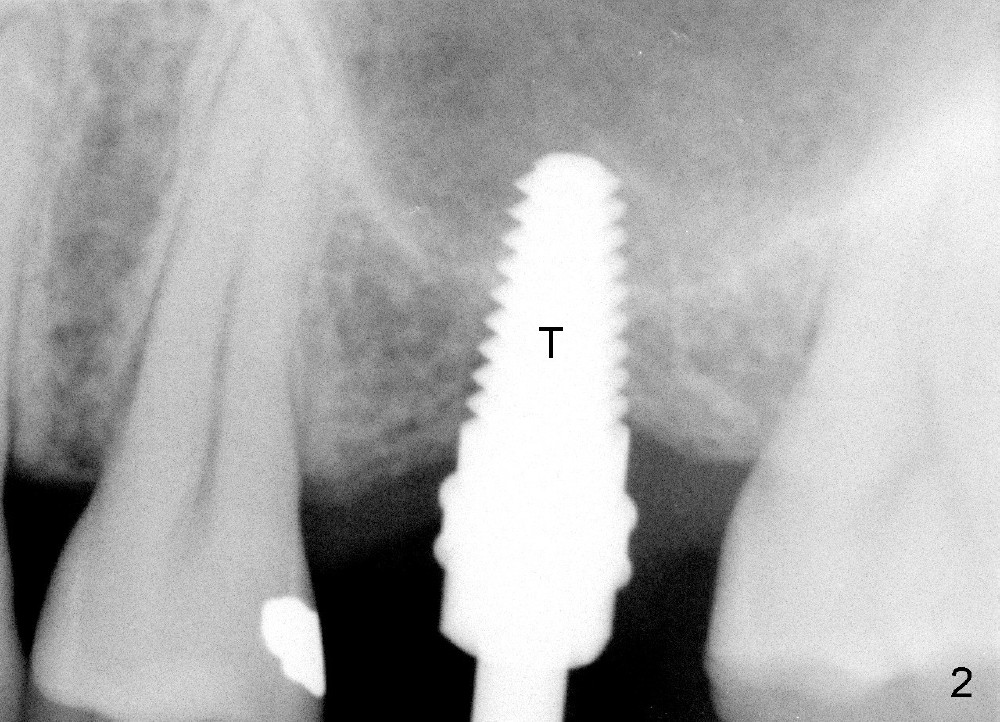

A 45-year-old man has lost the tooth #14 for a while (Fig.1); bone height is 5.4 mm. An extra wide and short implant is planned. Torus palatinus is large, suggesting that bone density should be high. A 6 mm tissue punch is chosen, but it is placed more palatal. If it were placed in the middle of the ridge, there would be no buccal keratinized gingiva (incision may avoid this issue). Additionally, the buccal portion of punch is made incomplete so that there is pedicle on the buccal side when the flap is raised (Fig.4,8: F). It is expected that the excess portion of keratinized tissue will form thick gingiva buccally. Osteotomy proves that bone is dense (Fig.2 (4.5x11 mm tap). Typical sinus lift is finished with placement of 6.4x6 mm (extra wide) bone-level implant (Fig.3, >55 Ncm). Following further torque, Fig.4 shows that the implant (I) is sub-gingival (<). Bitewings are taken to confirm that the implant plateau is at the crestal level (Fig.5,6 ^). PA shows sinus lift (Fig.7 *). The lingual aspect of the implant and healing abutment (H) is further bone grafted and covered by collagen dressing (Fig.8 *). The wound is protected with perio dressing. When the latter dislodges 7 days postop, the collagen dressing and bone graft are lost as well (Fig.10), while the buccal flap remains vital (Fig.9). The lingual exposed plateau should be able to heal normal. The collagen dressing should have been fixed in place by suture or as simple as a dental floss. There is mild nasal hemorrhage 1-2 days postop, possibly related to sinus membrane perforation and inability of Collagen Dressing to cover the perforation and contain the bone graft. When the patient returns for #9 implant placement in 3 weeks postop, the buccal flap reduces in size (Fig.11 *), while the palatal wound has healed with minimal exposure of the implant (Fig.12). Sinus graft remains in place 3 months postop (Fig.13); the buccal flap appears to have incorporated into a part of the gingiva (Fig.14). The bone density of the sinus lift appears to increase 10 days later when an abutment is placed (Fig.15 *). Although oral hygiene is pristine, there is apparent crestal bone resorption 12 months (Fig.16) and 20 months (Fig.17) post cementation, probably due to unfavorable crown/implant ratio and bruxism as well as pre-implantation bone loss (Fig.18,19). In contrast, an immediate implant in the same patient avoids pre- or post-implantation bone loss. In fact both the soft (Fig.20) and hard (Fig.21) tissues remain healthy 2 years 8 months post cementation. The sinus lift remains 3 years 8 months post cementation (Fig.22), while the crestal bone loss persists. The patients keeps complains of food impaction distal associated with bad smell 4 years 1 month post cementation. In fact the distal proximal contact is within normal limit. The bad smell is probably due to crestal bone loss (Fig.23 (pan), 24 (CT) *) and periimplantitis. Bone graft, PRF and Cytoplast membrane will be needed and fixed in place with long healing screw. When the patient returns for crown redo, he also reveals floss related gingival hemorrhage. There is pain associated with palatal sulcus probing with light gingiva erythema. Review of CT coronal section shows possible palatal (Fig.25 P) bone loss (*).